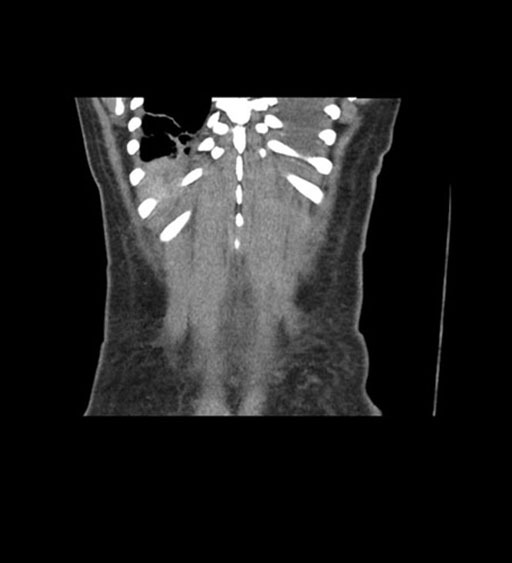

Coronal Arterial

Coronal Venous